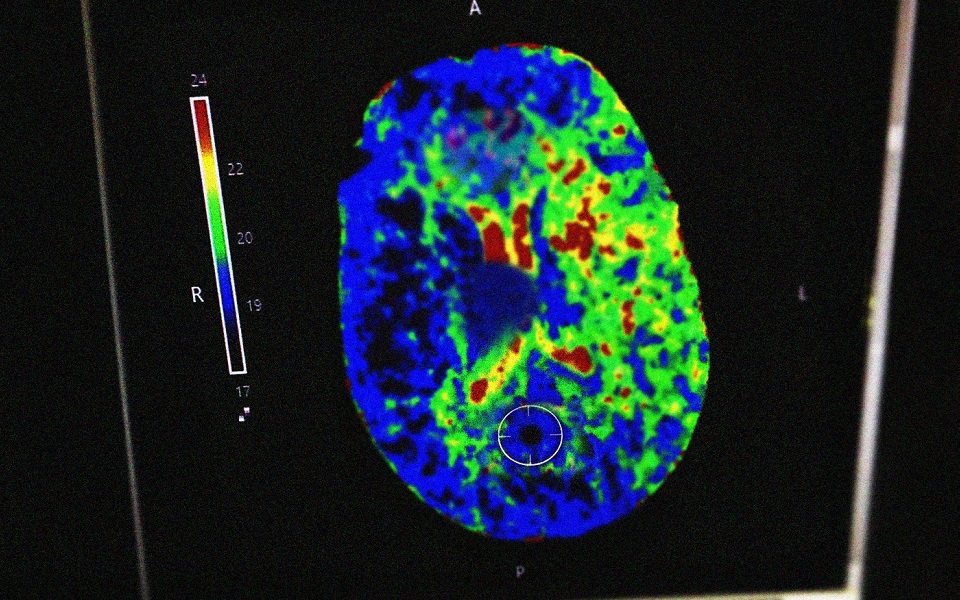

В Рязанской ОКБ врачи оказали помощь пациентке с инсультом. Об этом сообщили в пресс-службе минздрава Рязанской области.

Женщине стало плохо на улице. Прохожие, находившиеся рядом, вызвали бригаду скорой помощи. Пациентку доставили в больницу с нарушением мозгового кровообращения.

Специалисты осмотрели рязанку и диагностировали у нее инсульт, после чего начали готовить ее к тромболизису – препарат растворяет тромб, который стал причиной инсульта.

Оперативное лечение позволило женщине перенести инсульт без последствий. В настоящее время она выписана для наблюдения по месту жительства.

Иллюстрации:  Минздрав Рязанской области